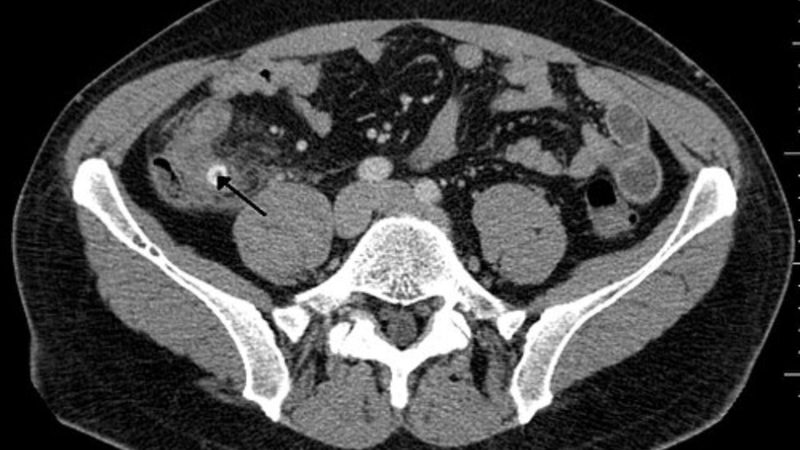

Để đánh giá mức độ và loại trừ biến chứng, bác sĩ sẽ chỉ định làm thêm các thăm dò cận lâm sàng như chụp X quang bụng, siêu âm hoặc CT scan, nội soi đại tràng… Tùy thuộc vào nhận định ban đầu, bác sĩ sẽ chỉ định phương pháp phù hợp.